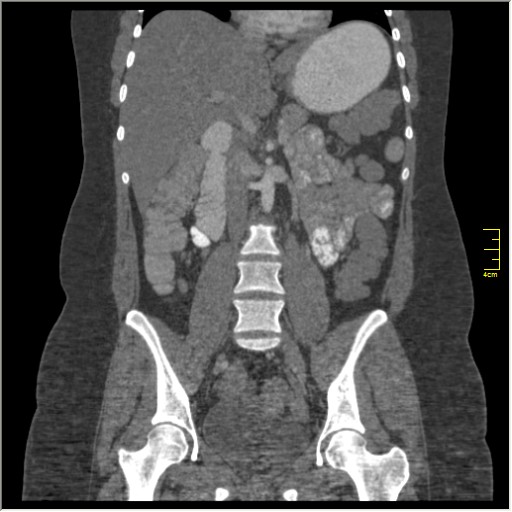

КТ энтерография

Демонстрационные изображение, оцените возможности метода! Толщина среза реконструкции 0.5-1 мм.